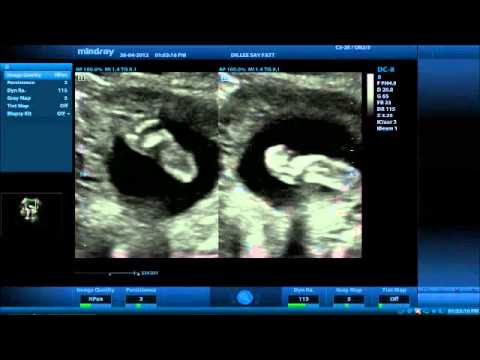

[最も選択された] 24 Weeks Pregnant Ultrasound Report 248737-24 Week Pregnancy Usg Report

It is normally performed between 21 24 weeks gestation as this is the best opportunity during pregnancy to examine all the anatomy of your baby in great detail It is not necessary for you to have a full bladder for this scan The anatomy or week scan is a transabdominal scan and is noninvasive procedure

24 week pregnancy usg report- A total of 529 women who underwent a routine ultrasound scan at 11–14 weeks and at 22–24 weeks, and for whom the outcome of pregnancy was fully known, were included in the analysis The scans included fetal examination and the option of having a transvaginal scan to measure cervical length as a screening test for spontaneous preterm delivery Week 11 to 13 During 11 to 13 weeks of pregnancy, a regular blood pressure check up and weight are measured During pregnancy, a weight gain of around 11 to 16 kg is considered good for person with normal BMI (pregnancy BMI 185 to 249) The amount of weight gain will help to understand the growth of the baby